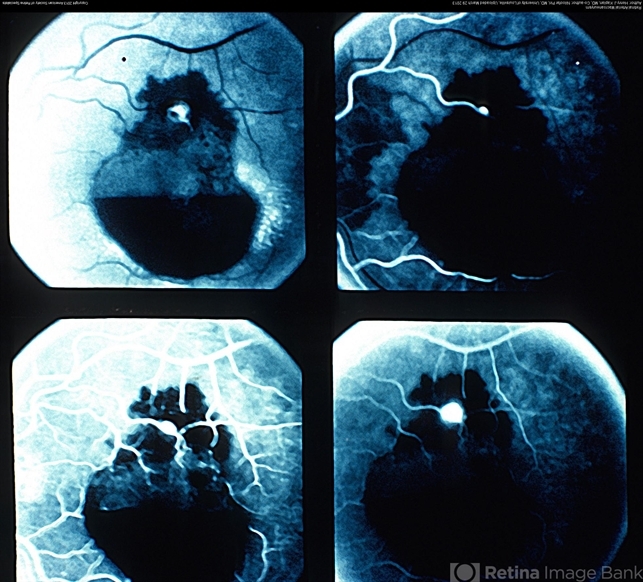

- macroaneurysm, retinal arterial macroaneurysm

- Fluorescein angiogram of a retinal arterial macroaneurysm with both subretinal (subretinal blocked fluorescence in the superior part) and subhyaloid hemorrhage (boat shaped blocked fluorescence in the inferior part).